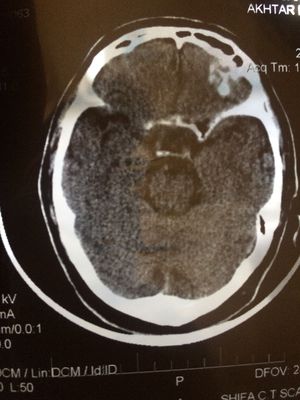

What is this wite thing in the left side of the frontal area? The dg is frontal sunisitis at right.

the white thng is the calcification... bt i think this is not the frontal sinus because it lies in front of this whte thing..